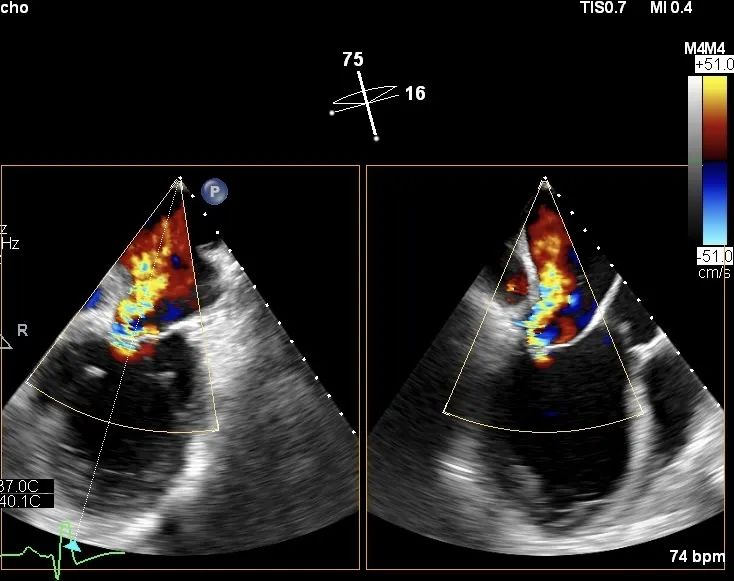

图片

患者术前二尖瓣重度返流(4+)